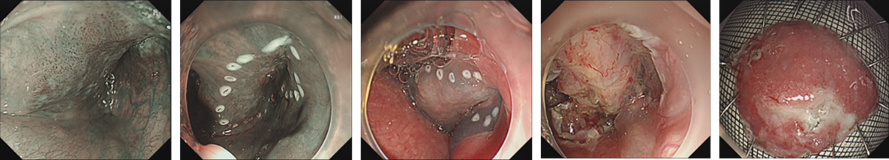

结合病变特征(局限于黏膜层、无淋巴结转移),符合内镜下治疗指征,经患者及家属同意后,对右侧下咽部早期癌行ESD 手术治疗。

image.png

图2 右侧下咽部早期癌ESD手术